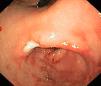

During this 5-year period, 5 patients received a diagnosis of EG. All were male, and they were aged 1–13 years. Two had underlying disease: one had undergone multivisceral transplantation, and the other had type 1 diabetes. The most frequent symptom was vomiting, found in 4 patients (80%), followed by abdominal pain in 2 (40%), faltering weight in 2 (40%), abdominal distension with ascites in 1 (20%) and diarrhoea in 1 (20%). The median duration of symptoms was 2 months (range, 1–5). All patients had serum albumin levels at the threshold of hypoalbuminaemia and 80% had peripheral blood eosinophilia. One patient had elevated IgE (111kU/L) with a positive skin test for cow's milk protein allergy. Microbiological testing was negative in all. The ultrasound examination revealed increased thickness of the gastrointestinal tract wall (at the level of the pylorus in 2, the gastric antrum and duodenum in 2, and the small intestine in 1). The endoscopic examination revealed a swollen and nodular mucosa in all patients, pyloric stenosis in 3, duodenal stenosis in 1, and duodenal ulcer in 1 (Figs. 1 and 2). Microscopic examination of biopsies revealed eosinophilic infiltration in the oesophagus in 80%, in the stomach in 100%, and in the small bowel in 60%. All patients were treated with glucocorticoids (oral methylprednisolone at 1–2mg/kg/day tapered off over 2 months) with a favourable response; the disease recurred in 3 patients, who required an additional course of glucocorticoids. As adjuvant treatment, 2 were fed with extensively hydrolysed casein formula, 2 received antisecretory drugs, and 1 underwent pyloroplasty.

Eosinophilic gastroenteritis is an uncommon disease characterised by continuous or patchy eosinophilic infiltration of the gastrointestinal tract. Its aetiology remains unknown. Several hypotheses have been proposed; the most widely accepted posits that it involves an immediate or type I hypersensitivity reaction to food allergens. We only found evidence of sensitisation to cow's milk protein in 1 of our patients. Its incidence is estimated at around 1–20 cases per 100000 births.1 Its clinical manifestations depend on the extent, location and depth of the inflammatory infiltrate. The gastric antrum and small bowel are the areas involved most frequently. It can be classified into 3 forms based on the depth of eosinophilic infiltration: mucosal disease (the most common, manifesting with abdominal pain, diarrhoea, weight loss and malabsorption), muscular layer disease (thickening of intestinal wall manifesting with symptoms of obstruction, usually at the level of the pylorus) and subserosal disease (transmural infiltration with development of eosinophilic ascites).2 Four of our patients had symptoms of obstruction, an unusual presentation,3 and one had features of ascites on ultrasound examination. Many cases also manifest with peripheral eosinophilia and protein-losing enteropathy. It is diagnosed based on the presence of gastrointestinal symptoms and histologic evidence of eosinophilic infiltration in one or more areas of the gastrointestinal tract in the absence of another cause of eosinophilia (parasitic disease, drug allergy, hypereosinophilic syndrome, coeliac disease or neoplasia). Imaging tests may reveal thickening of the mucosa and intestinal ulceration or partial obstruction. Endoscopic findings include oedema and congestion, and less frequently ulcerous lesions and narrowed areas (pylorus/duodenum).4 Microscopic examination of biopsy samples reveals a dense eosinophilic inflammatory infiltrate, with gastroenteropathy defined as presence of 25–30 or more eosinophils per high power field.5 Collection of multiple biopsy samples (at least 6) from each segment is recommended, as involvement may be patchy. Its management is based on dietary restrictions and treatment with glucocorticoids and immunosuppressive drugs.6 A high percentage of patients experience recurrence on discontinuation of steroid therapy and require an additional course of glucocorticoids or maintenance treatment with budesonide or azathioprine. Some cases of localised EG with muscle-layer involvement may require surgical correction of bowel obstruction, as was the case in one of our patients.